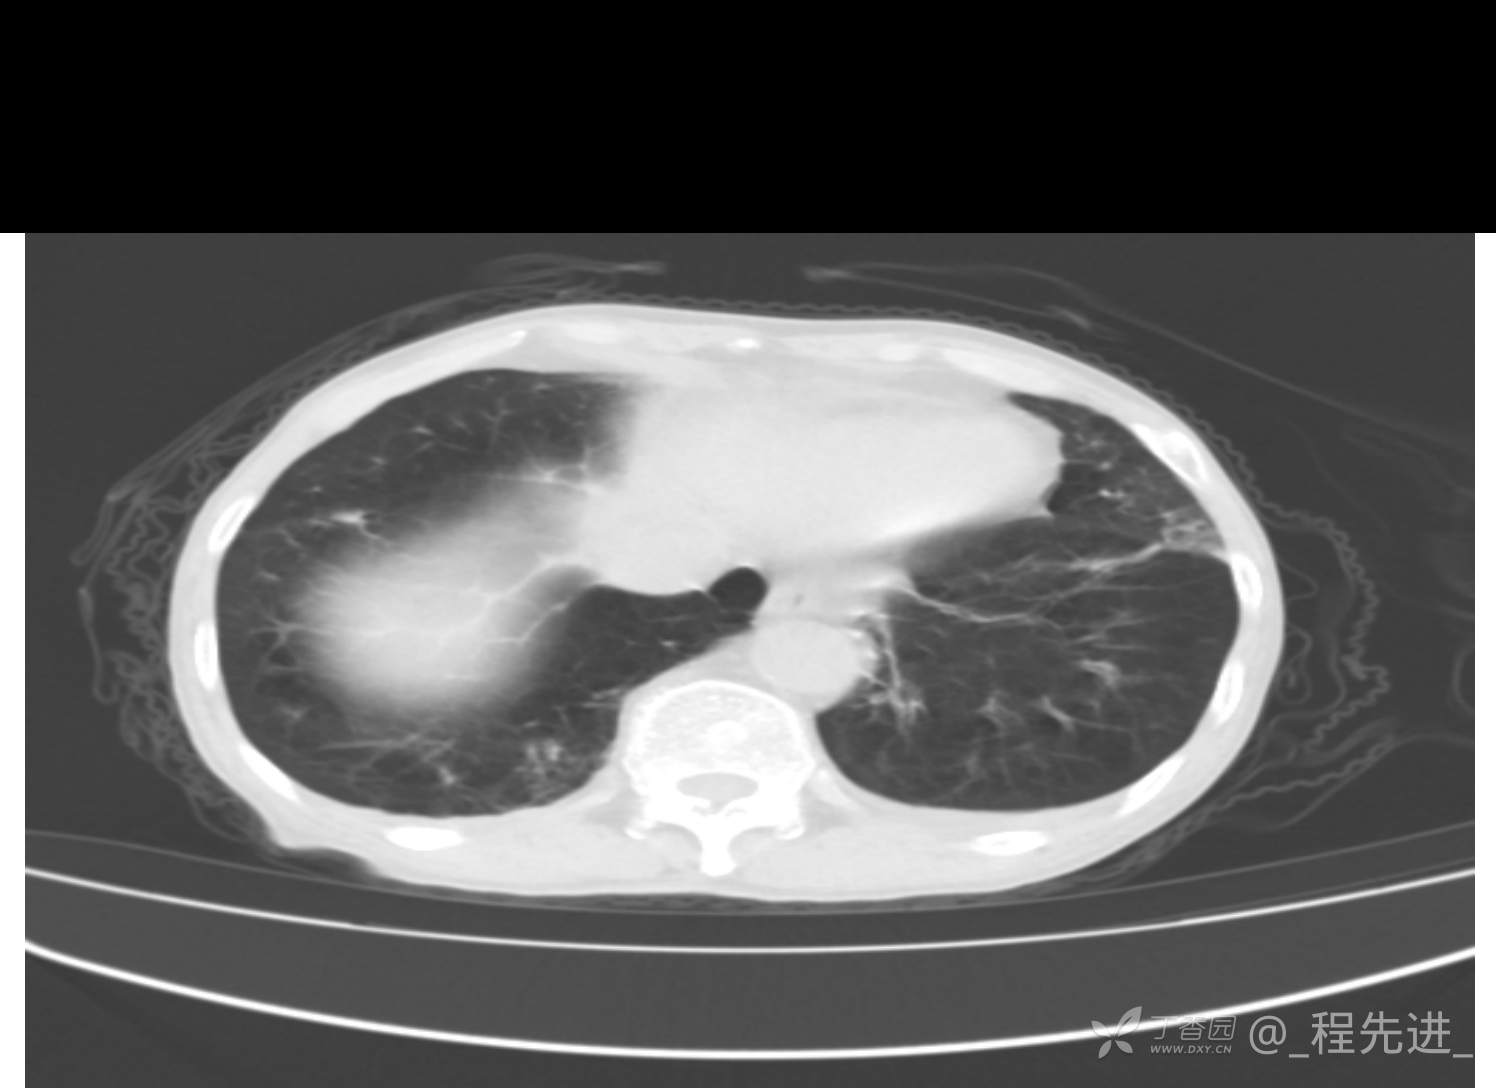

患者性别:男

患者年龄:81岁

简要病史:反复咳嗽、咳痰20余年,加重1周。两肺呼吸音低,可闻及散在干湿啰音。